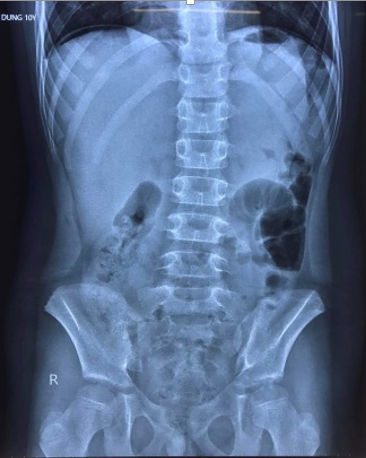

đã tiếp nhận hội chẩn từ xa từ Trung tâm y tế huyện Tiên Lãng 1 trường hợp: Bệnh

nhi 10T, Sars-CoV-2 (+) , xuất hiện đau bụng dữ dội vùng trên rốn kèm sốt, nôn 1

ngày, Chụp Xquang có hình ảnh liềm hơi dưới vòm hoành 2 bên , nghi ngờ thủng tạng

Liềm

hơi dưới vòm hoành 2 bên trên phim chụp Xquang là dấu hiệu rất có giá trị trong

chẩn đoán thủng tạng rỗng